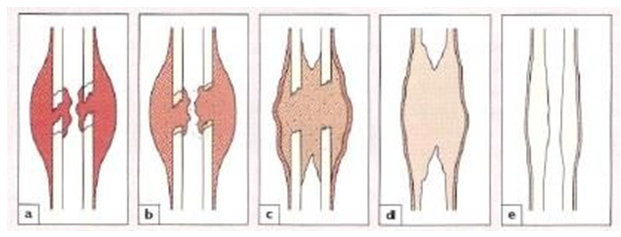

Topik 4 sains sukan

Bab 5 luka & patah

Jenis Dan Kategori Tulang Patah

Jenis Dan Kategori Tulang Patah